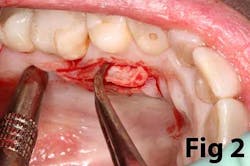

Surgical reconstruction of a deficient ridge/site begins with bone augmentation (i.e., lateral ridge graft, sinus augmentation, etc.), closely followed by soft-tissue augmentation (i.e., onlay graft, pedicle graft, etc.) When either cannot produce adequate ridge form for esthetics, prosthetic solutions are used to compensate for this deficiency. Soft-tissue augmentation, particularly those procedures to increase AG, is often overlooked.